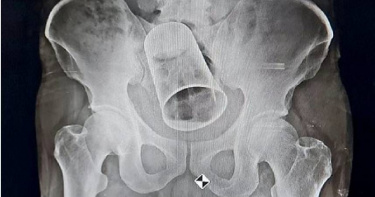

酒醉朋友惡作劇「塞鋼杯進男子直腸」 竟拖10天才就醫

鋼杯塞入直腸真的是遭朋友惡作劇,還是自己太愛玩?近日印度有名男子聲稱,他酒醉被朋友惡作劇,朋友把鋼杯塞入他的直腸中,10天後男子才到醫院就醫,經手術後順利取出。據《每日郵報》報導,印度百利帕達爾(Ballipadar)一位45歲的男子,近日在當地醫院手術取出了鋼杯,他表示,因為酒醉朋友惡作劇,把鋼杯塞到他的直腸,這個鋼杯直徑有8公分,長15公分。當地媒體報導,男子家人在知道有鋼杯在他的直腸後,馬上送他去醫院,男子因為怕就醫太尷尬所以拖了10天,而鋼杯卡在男子直腸中,害他的胃開始腫脹,也無法順利排便。據了解,男子跟朋友在古吉拉特邦喝酒,該城邦規定禁止飲酒。從醫院的X光片照來看,男子的直腸卡了一個鋼杯,讓人看了難以置信。起初,醫師想直接取出鋼杯,但鋼杯太大了所以不得不進行腸道切割手術,手術時間花了2.5小時,目前男子正在康復中,病情穩定。